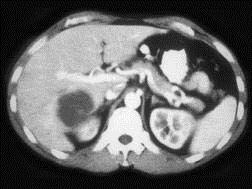

问题 女,58岁,肝区疼痛半月,发热,白细胞升高,CT检查如图,请选择最可能诊断 ( )

选项 A、肝转移瘤 B、肝棘球蚴病 C、肝囊肿 D、肝脓肿 E、原发性肝癌

答案 D